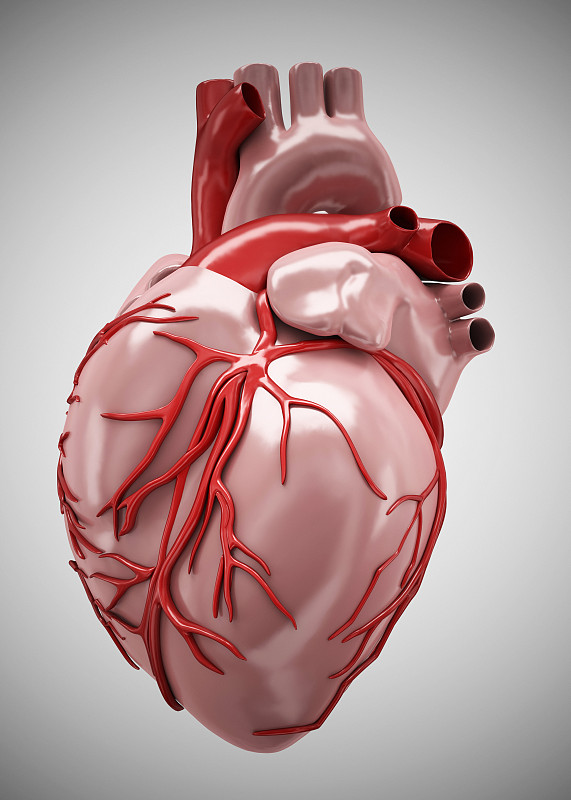

心详情

3d插图的视觉效果详情

JPG

3d插图的视觉效果详情

JPG